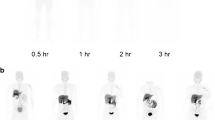

In average, (2.4 ± 0.1) MBq per kg bodyweight (range: 2.3–2.5 MBq/kg) were injected. Organs showed in general low uptakes, see Fig. 2a, while the renal cortices were clearly visible with a SUV of in average (8.6 ± 2.3) after 30 min (average of all left and right kidneys), which slowly dropped over time until a SUV of (1.3 ± 0.2) after the full examination time of 270 min. All according time activity curves including heart are presented in Fig. 2b.

Dynamic series of static images of [18F]Me4FDG. a: dynamic series of static images of [18F]Me4FDG showing the biodistribution of this tracer. The first image represents a sum of the first 30 min. b: dynamic uptake behavior, with the renal parenchyma showing the highest uptake at the beginning of the tracer injection. Mean SUV of all referring regions is shown. SUV: standardized uptake value

In Fig. 3, the dose of [18F]Me4FDG from one representative female subject is shown 270 min after injection. The calculated effective dose was in total (0.013 ± 0.003) mSv/MBq. The organs with the highest absorbed dose were the kidneys with 0.05 mSv/MBq per kidney while the brain showed almost no uptake, see Fig. 3; Table 2. After 60 min, 12 ± 15% of the administered dose was excreted into the bladder. For the individual uptake of all organs that had visible tracer uptake, see Table 2.